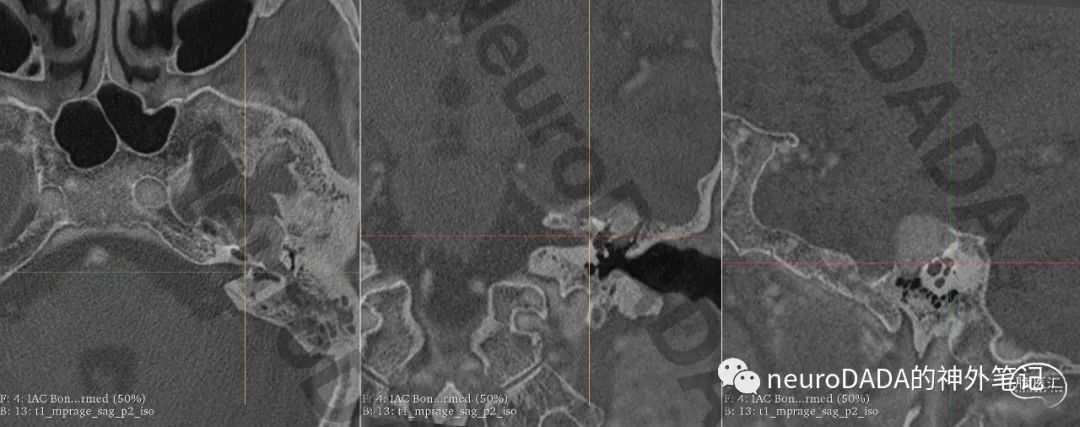

颞骨CT,不对劲嘛,右侧卵圆孔有明显异常啊,赶紧slicer重建走起。

一目了然,右侧卵圆孔颅外面有情况!而这正是我等候多年的卵圆孔颅外口两大解剖变异之一的“pterygoalar bar”(翼突-蝶骨大翼骨赘)!

术后复查CT可见手术目的达成。右侧卵圆孔颅外面的骨赘消失了。